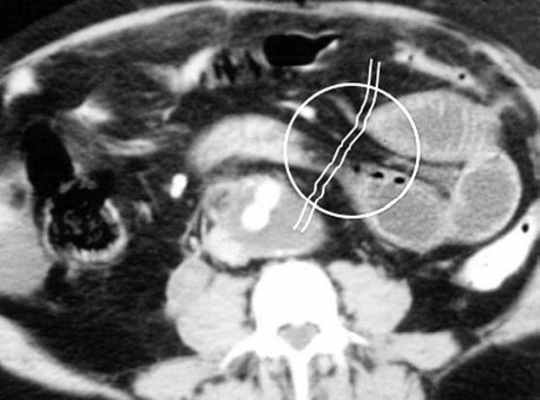

Осложнённая форма (чаще всего в результате странгуляции)

Для странгуляции тонкой кишки характерны утолщение стенок кишечника, васкулярные нарушения и выраженные патологические изменения в брыжейке и в брюшной полости. Диагностические находки включают в себя:

-расширенные петли тонкой кишки проксимальнее транзиторной зоны (зоны обструкции);

-спавшиеся петли кишечника дистальнее уровня обструкции;

-транзиторная зона;

-смешанный характер стаза содержимого кишечника в расширенных петлях с преобладанием жидкостного компонента;

-утолщение стенки кишки циркулярного типа. Важно помнить, такой тип утолщения стенок тонкой кишки при непроходимости как правило связан с сосудистыми нарушениями;

-нарушение нормального контрастного усиления стенок кишки. Изменения варьируют от гиперконтрастирования до полного отсуствия контрастного усиления. Различные варианты этих изменений между описанными выше крайностями могут наблюдаться одновременно в разных сегментах тонкой кишки. Полное отсутствие усиления означает артериальный рефлекторный спазм и свидетельствует в пользу тяжести поражения;

-петля с утолщенными стенками теряет свою эластичность и становится ригидной, вытянутой;

-пристеночный пневматоз тонкой кишки, в особо тяжелых случаях появляются интрамуральные пузырьки газа;

-появление патологических плотностей в брыжейке в виде распространяющихся матовых инфильтратов и тяжистости за счет кровоизлияний в жировые ткани;

-застойные изменения сосудов брыжейки. Сначала диаметр сосудов увеличивается, но со временем наступает рефлекторный артериальный спазм, брыжейка будет выглядеть с обеднённой васкуляризацией. Сосуды сужены или с полностью коллабированным просветом;

-газ в просвете верхней брыжеечной вены;

-газ в просвете портальной вены;

-при заворотах нарушается нормальная сосудистая анатомия брыжейки. Сосуды как бы закручиваются вокруг оси заворота и тянут за собой измененный брыжеечный жир- по типу раковины улитки или торнадо. Для большей наглядности представьте себе кусок расправленной ткани на столе, которую вы прижали пальцем и начали закручивать не отрывая ваш палец от стола. На КТ сканах часто можно увидеть характерный признак конусовидной спирали (whirl sign);

-свободная жидкость в карманах брыжейки и в брюшной полости. Иногда жидкость может быть повышенной плотности за счет геморрагического компонента.

примеры странгуляционной осложнённой непроходимости с характерными изменениями в брыжейке, внутрибрюшинном жире, утолщением стенок тонкой кишки и нарушением контрастного усиления.

Закручивание сосуда при завороте